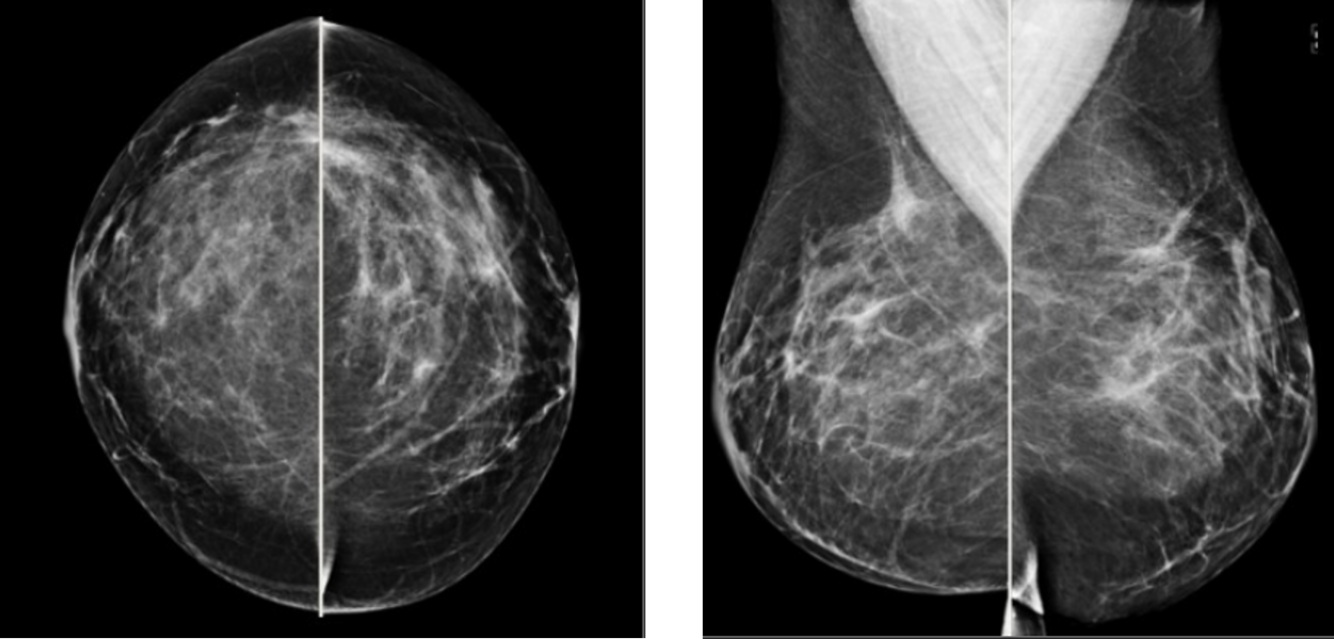

Bilateral reduction mammoplasty